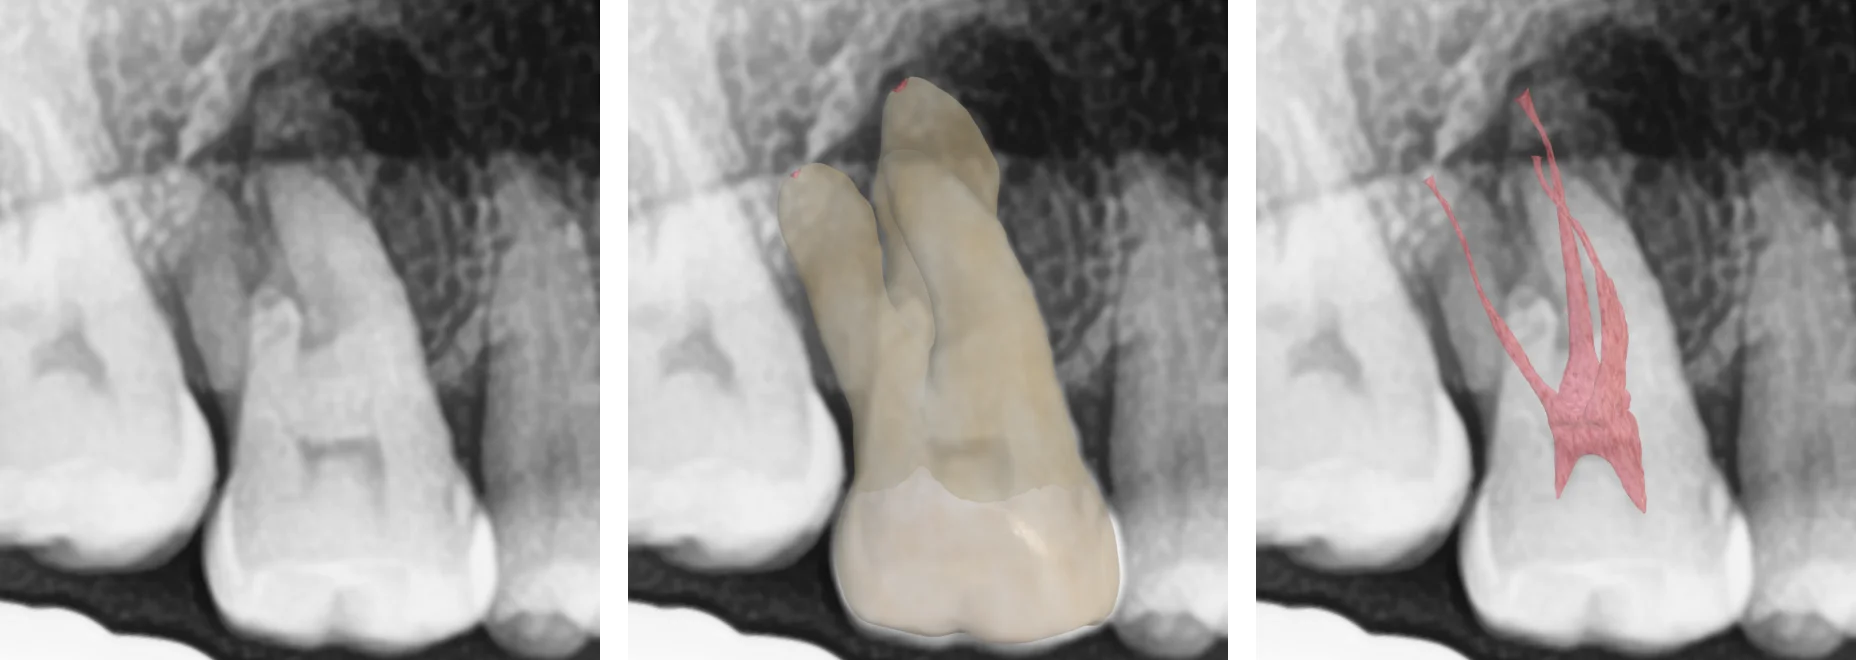

🏋️‍♂️ Exercise: Train Your Radiographic Vision!

Test your skills with this simple but effective exercise:

• Exercise 2

Dental x-ray, tooth and canal